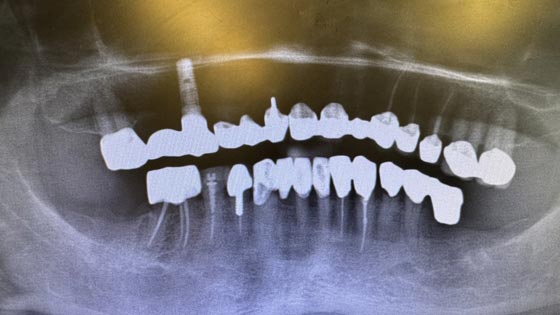

Implantat-Planung in 3D

Wir nutzen innovative 3D-Bildgebung für eine äußerst präzise Planung und gewährleisten von Einzelimplantaten bis hin zu Lösungen für Zahnlosigkeit einen stabilen Biss, wobei wir besonders auf alle anatomischen Strukturen achten.